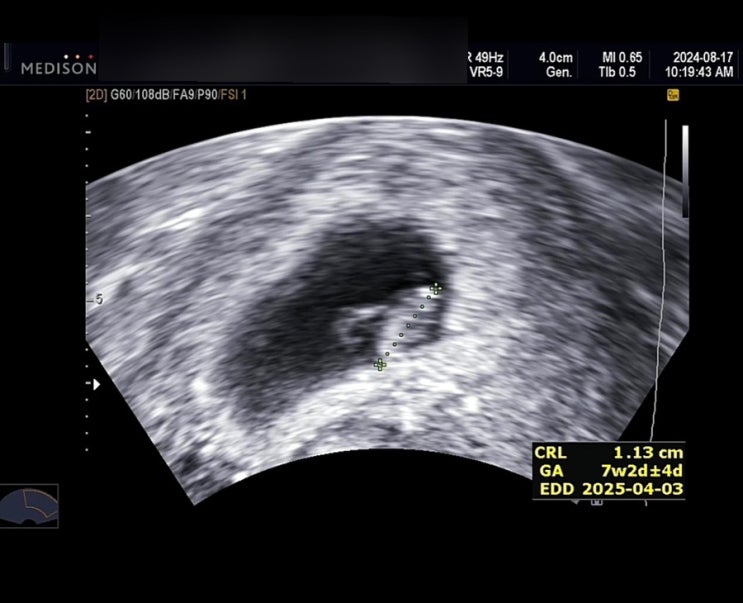

임신일기 7주차 8주차 9주차❤️

안녕하세요. 킴아입니다. 임신기간동안 기록 남겨두려고 임신일기 포스팅 쓰는중인데,, 초기 임신 4-6주를 ...